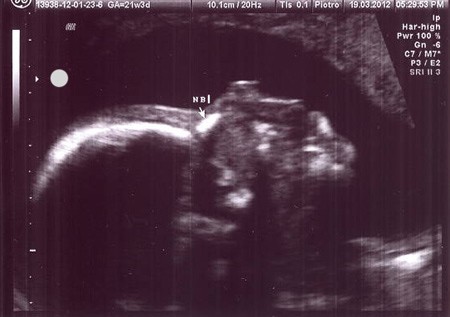

W macicy obecny jeden żywy płód w położeniu dowolnym, o wym.:

BPD – 42 mm

HC – 158 mm

AC – 133 mm

FL – 29 mm

odpowiada to 18-19 hbd

Serce czterojamowe FHR (+),plus. Cztery kończyny widoczne. Zarys czaszki i kręgosłupa prawidłowy.

Pęcherz moczowy i żołądek widoczne. Łożysko w trzonie macicy, na ścianie przedniej; I stopien dojrzałości. Aktywność ruchowa płodu prawidłowa.Ilość płynu owodniowego prawidłowa.

Biometria płodu nie jest zgodna z terminem porodu wyliczonym z OM.

Amna, czyli Bobas zdrowy, wszystko na miejscu :-). Gratulacje.